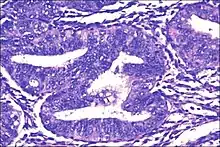

| Micrograph showing simple endometrial hyperplasia, where the gland-to-stroma ratio is preserved but the glands have an irregular shape and/or are dilated. Endometrial biopsy. H&E stain. | |

Endometrial hyperplasia is a condition of excessive proliferation of the cells of the endometrium, or inner lining of the uterus.

Like other hyperplastic disorders, endometrial hyperplasia initially represents a physiological response of endometrial tissue to the growth-promoting actions of estrogen. However, the gland-forming cells of a hyperplastic endometrium may also undergo changes over time which predispose them to cancerous transformation. Several histopathology subtypes of endometrial hyperplasia are recognisable to the pathologist, with different therapeutic and prognostic implications.[3]